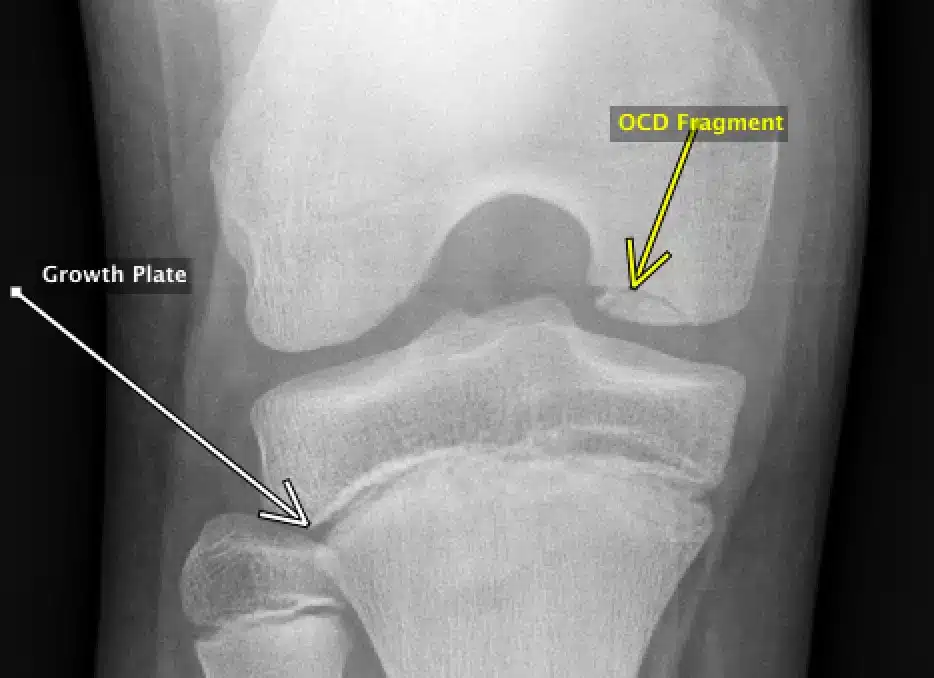

- رادیوگرافی (X-Ray): تصاویر رادیوگرافی ساده می توانند به بررسی اولیه مفصل و رد سایر مشکلات احتمالی مانند شکستگی استخوان کمک کنند.

- MRI (تصویربرداری رزونانس مغناطیسی): ام آر آی با ایجاد تصویری دقیق از مفصل، می تواند به تشخیص قطعی استئوکندریت و مشخص کردن اندازه، محل و وضعیت قطعه جدا شده استخوان و غضروف کمک کند.

استئوکندریت (Osteochondritis) یک اختلال مفصلی است که معمولاً نوجوانان و جوانان فعال را درگیر میکند. شایعترین نوع آن، استئوکندریت دیسکان (Osteochondritis Dissecans – OCD) نام دارد که در آن بخشی از استخوان زیر غضروف مفصل دچار آسیب شده و ممکن است تکهای از غضروف و استخوان جدا شود. این حالت منجر به درد، التهاب، و محدودیت حرکت در مفصل میشود.